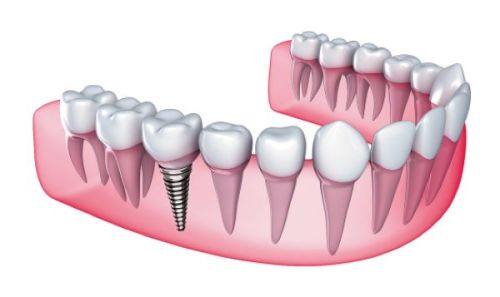

综合来看,合肥美奥口腔医院的口碑实力确实非常出色。它在技术、服务、价格等方面都表现得十分非凡。无论是牙齿矫正、种植牙,还是其他口腔疾病的治疗,医院都能够提供专精、效率高的解决方案。众多患者的真实反馈也证明了这家医院的实力和口碑。如果你正在为口腔问题而烦恼,不妨来合肥美奥口腔医院试试,相信它会给你带来满意的治疗成效。